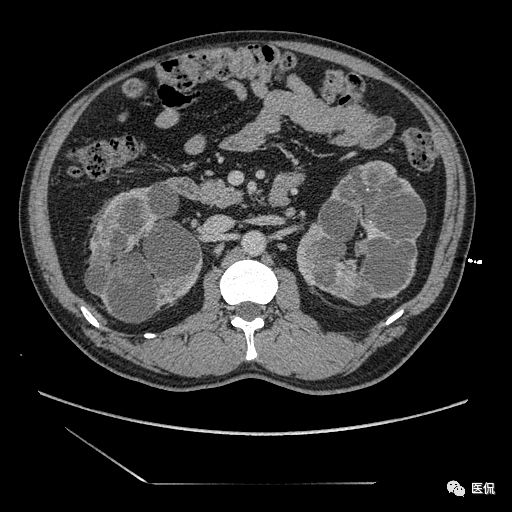

双肾实质可见多发囊性密度灶,其内密度不均匀,并可见钙化灶,增强扫描未见明显强化灶。肾周脂肪间隙清晰,与邻近组织分界清楚。

多囊肾的 CT 表现主要表现为双肾增大,轮廓光滑或有分叶,肾实质内多个大小不等的囊肿呈蜂窝状,多呈水样低密度,增强扫描囊肿本身无强化,而囊肿间正常肾组织增强,对比明显。当囊肿张力过高,使囊壁上毛细血管牵拉破裂出血时,表现为囊肿内稍高密度影,随访CT 值减低。囊壁钙化,表现为点线状高密度影像,随访CT值无变化。有文献报道约 30%病例可并发多囊肝或多囊胰。